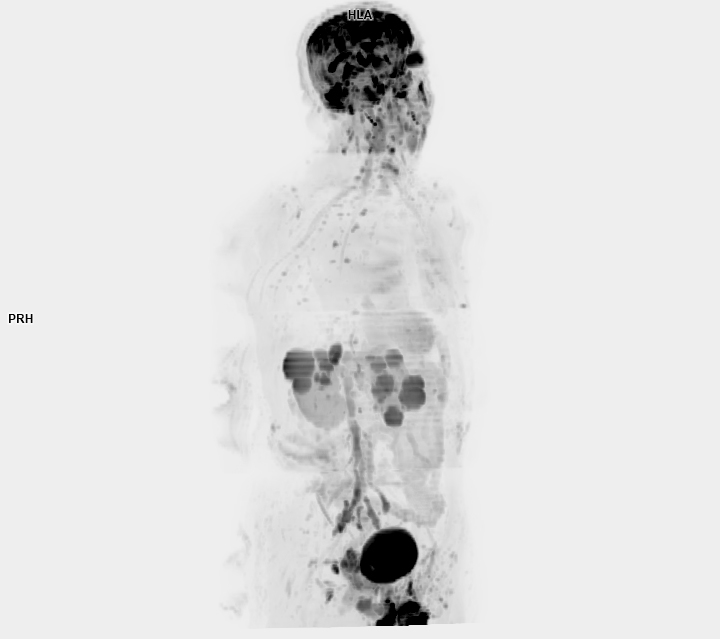

3 Tesla MR Çekim Görüntüleri

• 3 Tesla MR Çekim Görüntüleri